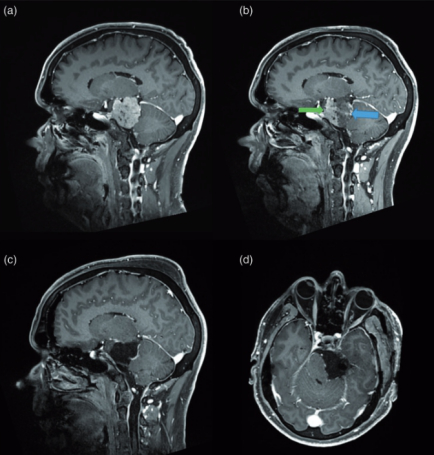

法国一位53岁男性,因三叉神经痛合并三叉神经感觉减退,在当地 神经外科医院 Lariboisiere医院,查出 左侧较大岩斜脑膜瘤 (27立方厘米)。脑磁共振(mri)显示...